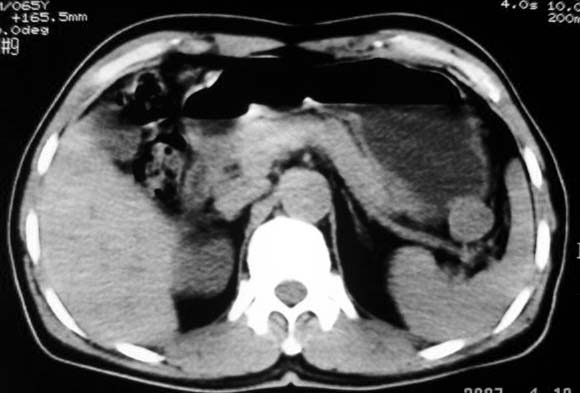

定位:病灶位于胃腔外,大弯侧后下方.

特征:实质性肿物,边界清楚,内见低密度影,明显压迫胃壁,并形成切迹.

考虑:脾门淋巴瘤或间质瘤.

胃大弯侧,胃底与胃体交界处可见一圆形软组织肿块影,边缘较光整,内部密度较均匀

考虑:胃平滑肌瘤

考虑:脾门淋巴瘤或间质瘤

考虑:胃间质瘤?息肉?

病灶起源于胃壁向腔内外突出,边缘光整,内可见片状低密度区,考虑胃壁非上皮性肿瘤可能性大

病灶起源于胃壁向腔内外突出,边缘光整,内可见片状低密度区,考虑间质瘤可能性大,建议增强扫描。